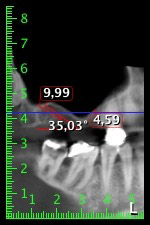

About six months after teeth 16 and 14 were extracted, a digital volume tomography (DVT, Planmeca) examination was performed for planning and risk minimization purposes. It clearly showed that the bone had not regenerated to the desired volume (Fig. 2 to 7).

To restrict the augmentation to region 14, and in consultation with the patient, it was planned that implant 16 would be placed, inclined, in the dorso-cranial direction (Fig. 8).